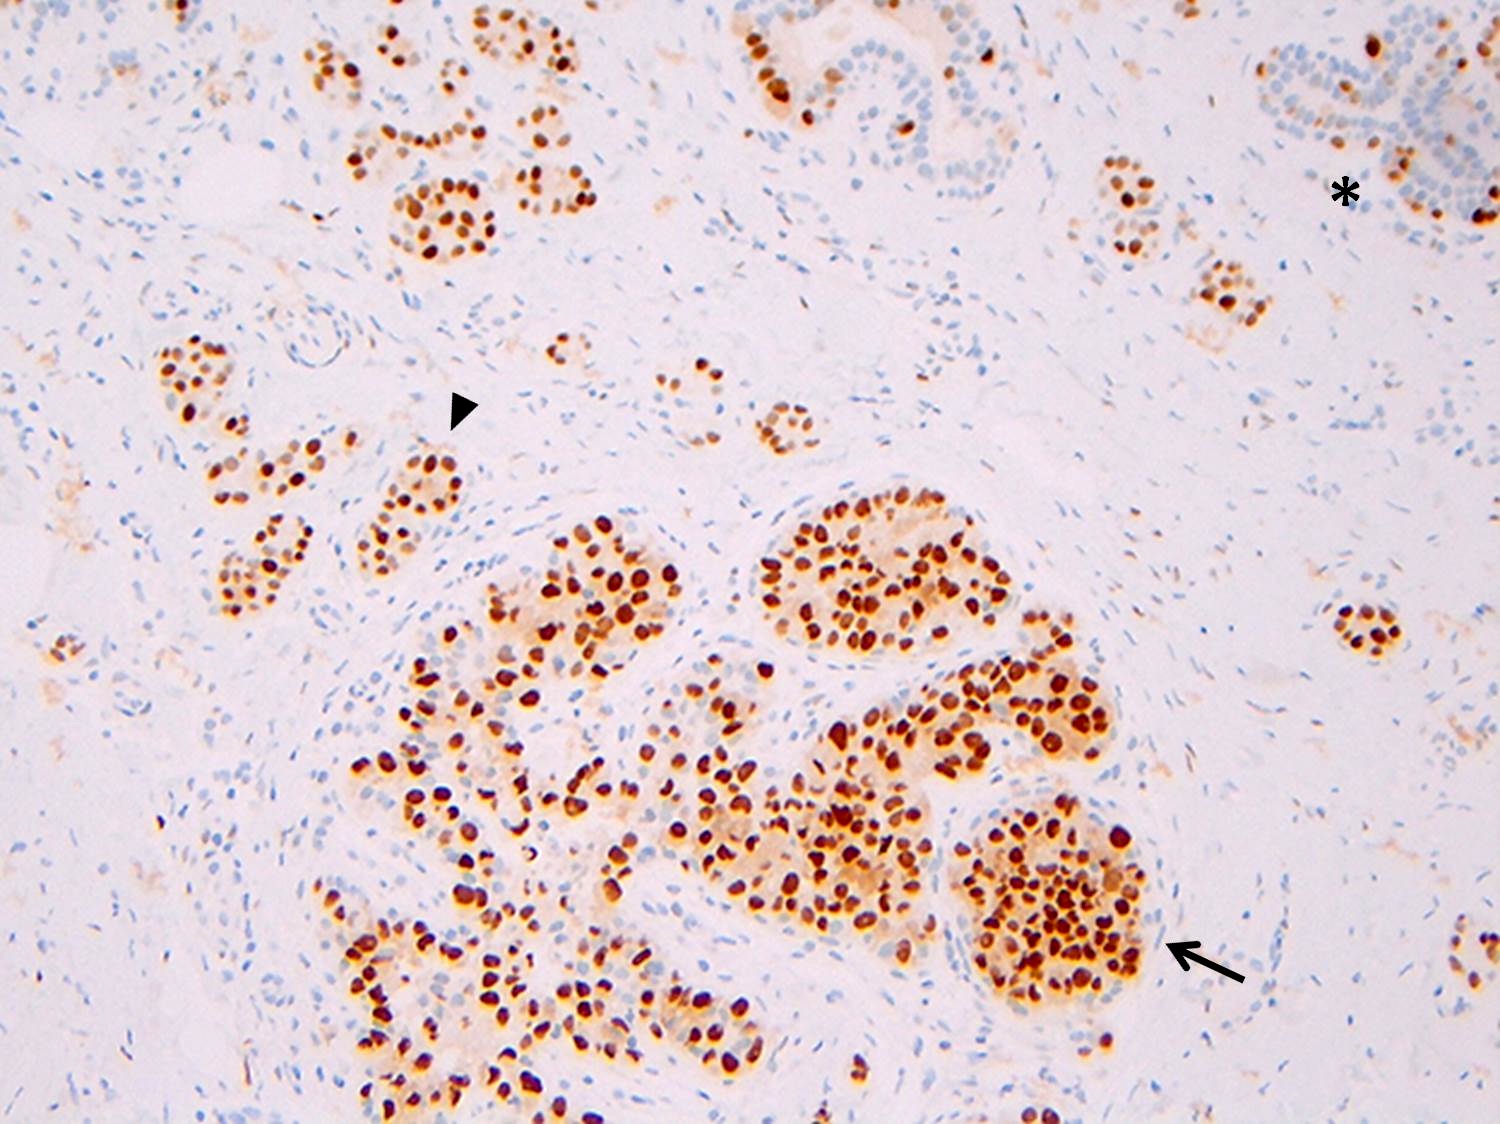

Microscopic (histologic) images

Contributed by Anna Biernacka, M.D., Ph.D.

Positive stains

- Strong and diffuse nuclear ER and PR, low Ki67 proliferation index (Cancer 1996;78:1403)

- p120 catenin in a cytoplasmic pattern (Arch Pathol Lab Med 2017;141:1668, Int J Clin Exp Pathol 2014;7:2551)

Negative stains

- E-cadherin: most cases of classic LCIS demonstrate complete loss of E-cadherin staining

- In some cases of classic LCIS, attenuated or aberrant E-cadherin expression is observed, with scattered cells that show dot-like discontinuous / weak membranous staining or patchy cytoplasmic staining

- Atypical E-cadherin patterns or membranous positivity do not preclude the diagnosis of classic LCIS (Surg Pathol Clin 2018;11:123)